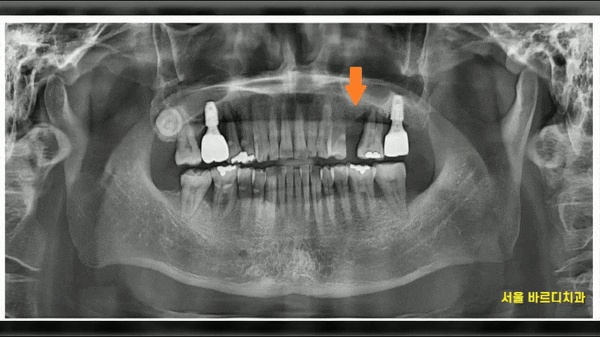

이미 치아 한개가 뽑힌 상태로

상일동 치과를 내원해주셨습니다.

치아 떼운 곳도 떨어지고

전반적으로 손봐야한다고 표현해주셨는데요.